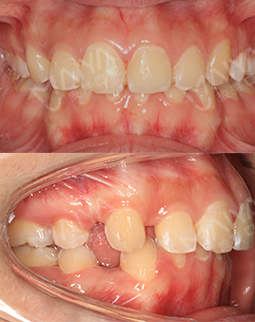

“以前牙不齐,两颗上门牙有点突,被人说是‘老鼠牙’,还有深覆颌(刚开始我不懂,后来做了小百科哈,如果你们跟我一样,牙齿咬合状态时,上门牙盖住了下门牙,超过了1/3就被称为深覆合),导致了我每次拍照的时候从来都不笑,一定要笑,也是笑不露齿的那种。

开门见山,20岁,坐标广东,“以前牙不齐,两颗上门牙有点突,被人说是‘老鼠牙’,还有深覆颌(所谓的深覆合就是牙齿咬合状态时,上门牙盖住了下门牙,一般1/3是比较正常的,超过了1/3就被称为深覆合),导致了我每次拍照的时候从来都不笑,一定要笑,也是笑不露齿的那种。”真的很像假笑女孩~[○・`Д´・ ○].牙齿不齐,对口腔清洁也是非常遭罪,这个本人是深有体会啊